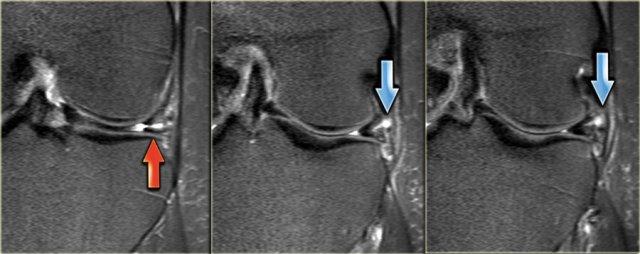

Bên trái là ba lát cắt coronal PD liên tiếp:

-

Rách bó dây chằng bên trong sâu (mũi tên vàng).

Bong mảnh xương ở mặt ngoài đầu gần xương chày, tức là gãy xương Segond (mũi tên đỏ). -

Lưu ý mảnh sụn chêm phía trong bị di lệch.

Điều này cho thấy còn có thêm rách dạng quai xô (bucket handle tear). -

Ngoài rách dạng quai xô (mũi tên xanh phía trong), còn có một đường rách ngang khó nhận thấy ở phần ngoại vi của sụn chêm (mũi tên xanh phía ngoài).

Đường rách ngang này được thể hiện rõ hơn trên các hình ảnh khác (không trình bày ở đây).

Tiếp tục xem các hình ảnh sagittal.

Gãy xương Segond gần như là dấu hiệu đặc trưng (pathognomonic) của rách dây chằng chéo trước, điều này cũng được ghi nhận ở bệnh nhân này.